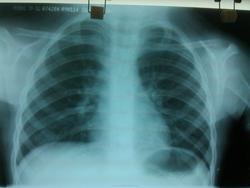

Пол пациента: Женский пол Тип патологии: Другое Область исследования: Грудная клетка и верхние дыхательные пути Методы исследования: Rg Ребёнок, девочка, 2г.7 мес. Пневмония? https://radiomed.ru/sites/default/files/styles/case_slider_image/public/user/18609/img_20140423_140304.jpg?itok=8-US-oze ID:37429 Wed, 23/04/2014 - 15:20 #1 Сергей Кузьминов Offline Last seen: 1 year 6 months ago Joined: 06.10.2012 - 15:51 Posts: 11813 Да.Справа внизу. Wed, 23/04/2014 - 16:17 #2 NIL Offline Last seen: 3 weeks 4 days ago Joined: 25.11.2013 - 20:50 Posts: 18217 Да, справа в нижней доле фокусная тень "Слушай всех, прислушивайся к немногим, решай сам".© Wed, 23/04/2014 - 16:44 #3 ren_gen Offline Last seen: 11 years 6 months ago Joined: 30.10.2010 - 19:17 Posts: 285 +1, согласен с коллегами Thu, 24/04/2014 - 20:36 #4 JJ Offline Last seen: 11 years 10 months ago Joined: 03.04.2014 - 20:35 Posts: 102 +1, тоже согласна Sat, 26/04/2014 - 11:29 #5 Доктор Ре. Offline Last seen: 10 years 7 months ago Joined: 15.04.2014 - 16:37 Posts: 129 пневмония справа в нижней доле в S10. Wed, 30/04/2014 - 02:23 #6 Nobody Offline Last seen: 11 years 6 months ago Joined: 15.03.2014 - 20:29 Posts: 2013 Сергей Кузьминов wrote: Да.Справа внизу. Хорошее такое, рентгенологическое заключение!) "Лишь утратив всё до конца, мы обретаем свободу." F.C. Wed, 30/04/2014 - 15:27 #7 Сергей Кузьминов Offline Last seen: 1 year 6 months ago Joined: 06.10.2012 - 15:51 Posts: 11813 Это не заключение.Мнение это в разговоре. Wed, 30/04/2014 - 22:59 #8 Сольвейг Offline Last seen: 3 years 11 months ago Joined: 05.02.2013 - 20:25 Posts: 2239 Nobody wrote: Сергей Кузьминов wrote: Да.Справа внизу. Хорошее такое, рентгенологическое заключение!) Тоже улыбнуло!

Да, справа в нижней доле фокусная тень

пневмония справа в нижней доле в S10.